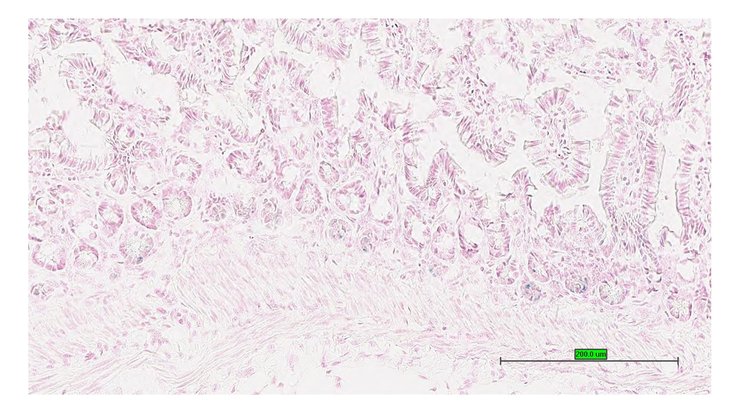

TS28: ileum Present UC Davis_1875594

Specimen UC Davis_1875595: postnatal adult; Ghtm1.1(KOMP)Vlcg/Gh+ (more )

Structure Level Pattern Image Note

TS28: ileum Present UC Davis_1875585

Specimen UC Davis_1875586: postnatal adult; Ghtm1.1(KOMP)Vlcg/Gh+ (more )

TS28: ileum Present UC Davis_1875586